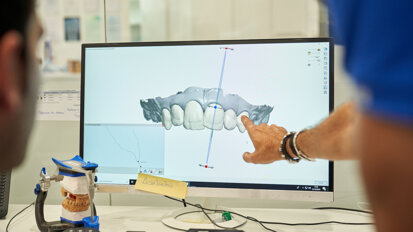

Aby uniknąć wielokrotnego łączenia i rozłączania elementów protetycznych i/lub filarów, sugeruje się obecnie umieszczenie filaru docelowego na etapie chirurgicznym i pozostawienie go bez interwencji, szczególnie u pacjentów z biotypem cienkim i średnim. W ten sposób umieszczenie filaru docelowego w momencie wszczepienia implantów powoduje, że zamiast 2 elementów powstaje jeden. Uzasadnieniem dla takiej zmiany postępowania jest wiedza o tym, że niestabilność tkanki miękkiej po wszczepieniu implantu może zagrażać uszczelnieniu wokół implantu i negatywnie wpłynąć na jego estetykę. W sytuacji, gdy dochodzi do zaburzenia szerokości biologicznej, spowodowanej wielokrotnym montażem filaru, tkanka łączna i łączący nabłonek mają tendencję do przesuwania się w stronę wierzchołka poza łączenie filaru z implantem (implant abutment junction – IAJ) dopóki znów nie znajdą miejsca, do którego będą mogły przylgnąć, co często powoduje zanik krawędzi kości, szczególnie w przypadku cienkiego biotypu dziąsła. Optymalną estetykę można osiągnąć wtedy, gdy filar docelowy zostanie umieszczony w momencie wszczepienia implantu i pozostanie nieruszony na etapie ostatecznej odbudowy. Ten sposób postępowania pomaga zachować strukturę kości i tkanki miękkiej. W tym zakresie coraz częściej stosowane są techniki kierowane modelami i komputerowo. Umożliwiają one opracowanie filaru implantologicznego w laboratorium przed wykonaniem zabiegu i zeskanowanie go (lub dokonanie wycisku) przed przyłączeniem. W ten sposób można wykonać prosty wycisk typu pick-up na etapie opracowywania korony bez uszkadzania uszczelnienia śluzówkowego, które cofa się – często kosztem kości wyrostka z wyjątkiem sytuacji, w których tkanka miękka jest gruba.

W zabiegach protetycznych należy unikać wielokrotnego mocowania i zdejmowania elementów protetycznych, a w kontakcie przezśluzówkowym należy stosować materiały zgodne biologicznie. Dlatego zalecane są systemy nawigacji komputerowej. Umożliwiają one opracowanie indywidualnie dopasowanych filarów wraz z odpowiednim wzorcem chirurgicznym oraz przygotowanie odbudowy tymczasowej w laboratorium przed dokonaniem interwencji chirurgicznej. W ten sposób filary można zeskanować lub pobrać ich wyciski przed pierwszym etapem, a następnie wykonać prosty wycisk typu pick-up korony ceramicznej kilka tygodni później – co nie zaburzy uszczelnienia śluzówkowego. Ponieważ stabilność tkanek wokół implantu jest złożonym problemem zależnym od wielu czynników, podsumowanie idealnego podejścia nie jest zadaniem łatwym. Aby rozwiązać ten problem na potrzeby codziennej praktyki implantologicznej, konieczne są dodatkowe prace badawczo-rozwojowe, a także lepsze zrozumienie środowiska biologicznego.

W artykule przedstawiono postępowanie kliniczne z użyciem skanera C.O.S.3M w rejestracji pola protetycznego z poziomu śruby gojącej Encode oraz w pełni...

W artykule przedstawiono postępowanie kliniczne z użyciem skanera C.O.S.3M w rejestracji pola protetycznego z poziomu śruby gojącej Encode oraz w pełni...